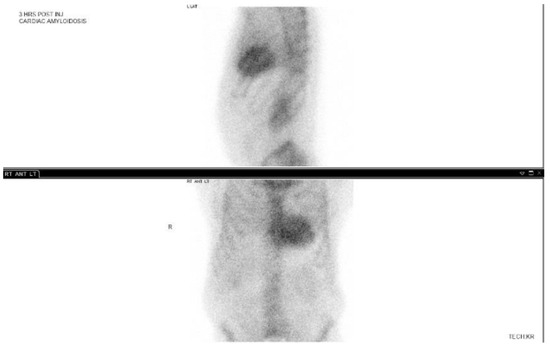

3.3. 99-Technetium Pyrophosphate Imaging

- Mori, A.; Saito, Y.; Nakamura, K.; Iida, T.; Akagi, S.; Yoshida, M.; Taniyama, M.; Miyoshi, T.; Ito, H. Microcalcification and 99mTc-Pyrophosphate Uptake without Increased Bone Metabolism in Cardiac Tissue from Patients with Transthyretin Cardiac Amyloidosis. Int. J. Mol. Sci. 2023, 24, 1921. [Google Scholar] [CrossRef]

- Masri, A.; Bukhari, S. Efficient 1-Hour Technetium-99 m Pyrophosphate Imaging Protocol for the Diagnosis of Transthyretin Cardiac Amyloidosis. Circ. Cardiovasc. Imaging 2020, 13, e010249. [Google Scholar] [CrossRef]

- Asif, T.; Gomez, J.; Singh, V.; Doukky, R.; Nedeltcheva, A.; Malhotra, S. Comparison of planar with tomographic pyrophosphate scintigraphy for transthyretin cardiac amyloidosis: Perils and pitfalls. J. Nucl. Cardiol. 2021, 28, 104–111. [Google Scholar] [CrossRef]

- Dorbala, S.; Ando, Y.; Bokhari, S.; Dispenzieri, A.; Falk, R.H.; Ferrari, V.A.; Fontana, M.; Gheysens, O.; Gillmore, J.D.; Glaudemans, A.W.; et al. ASNC/AHA/ASE/EANM/HFSA/ISA/SCMR/SNMMI Expert Consensus Recommendations for Multimodality Imaging in Cardiac Amyloidosis: Part 1 of 2—Evidence Base and Standardized Methods of Imaging. J. Card. Fail. 2019, 25, e1–e39. [Google Scholar] [CrossRef] [PubMed]

- Bokhari, S.; Castano, A. 99mTc-Pyrophosphate Scintigraphy for Differentiating Light-Chain Cardiac Amyloidosis From the Transthyretin-Related Familial and Senile Cardiac Amyloidoses. Circ. Cardiovasc. Imaging. 2013, 6, 195–201. [Google Scholar] [CrossRef] [PubMed]

- Gillmore, J.; Maurer, M. Nonbiopsy Diagnosis of Cardiac Transthyretin Amyloidosis. Circulation 2016, 133, 2404–2412. [Google Scholar] [CrossRef]